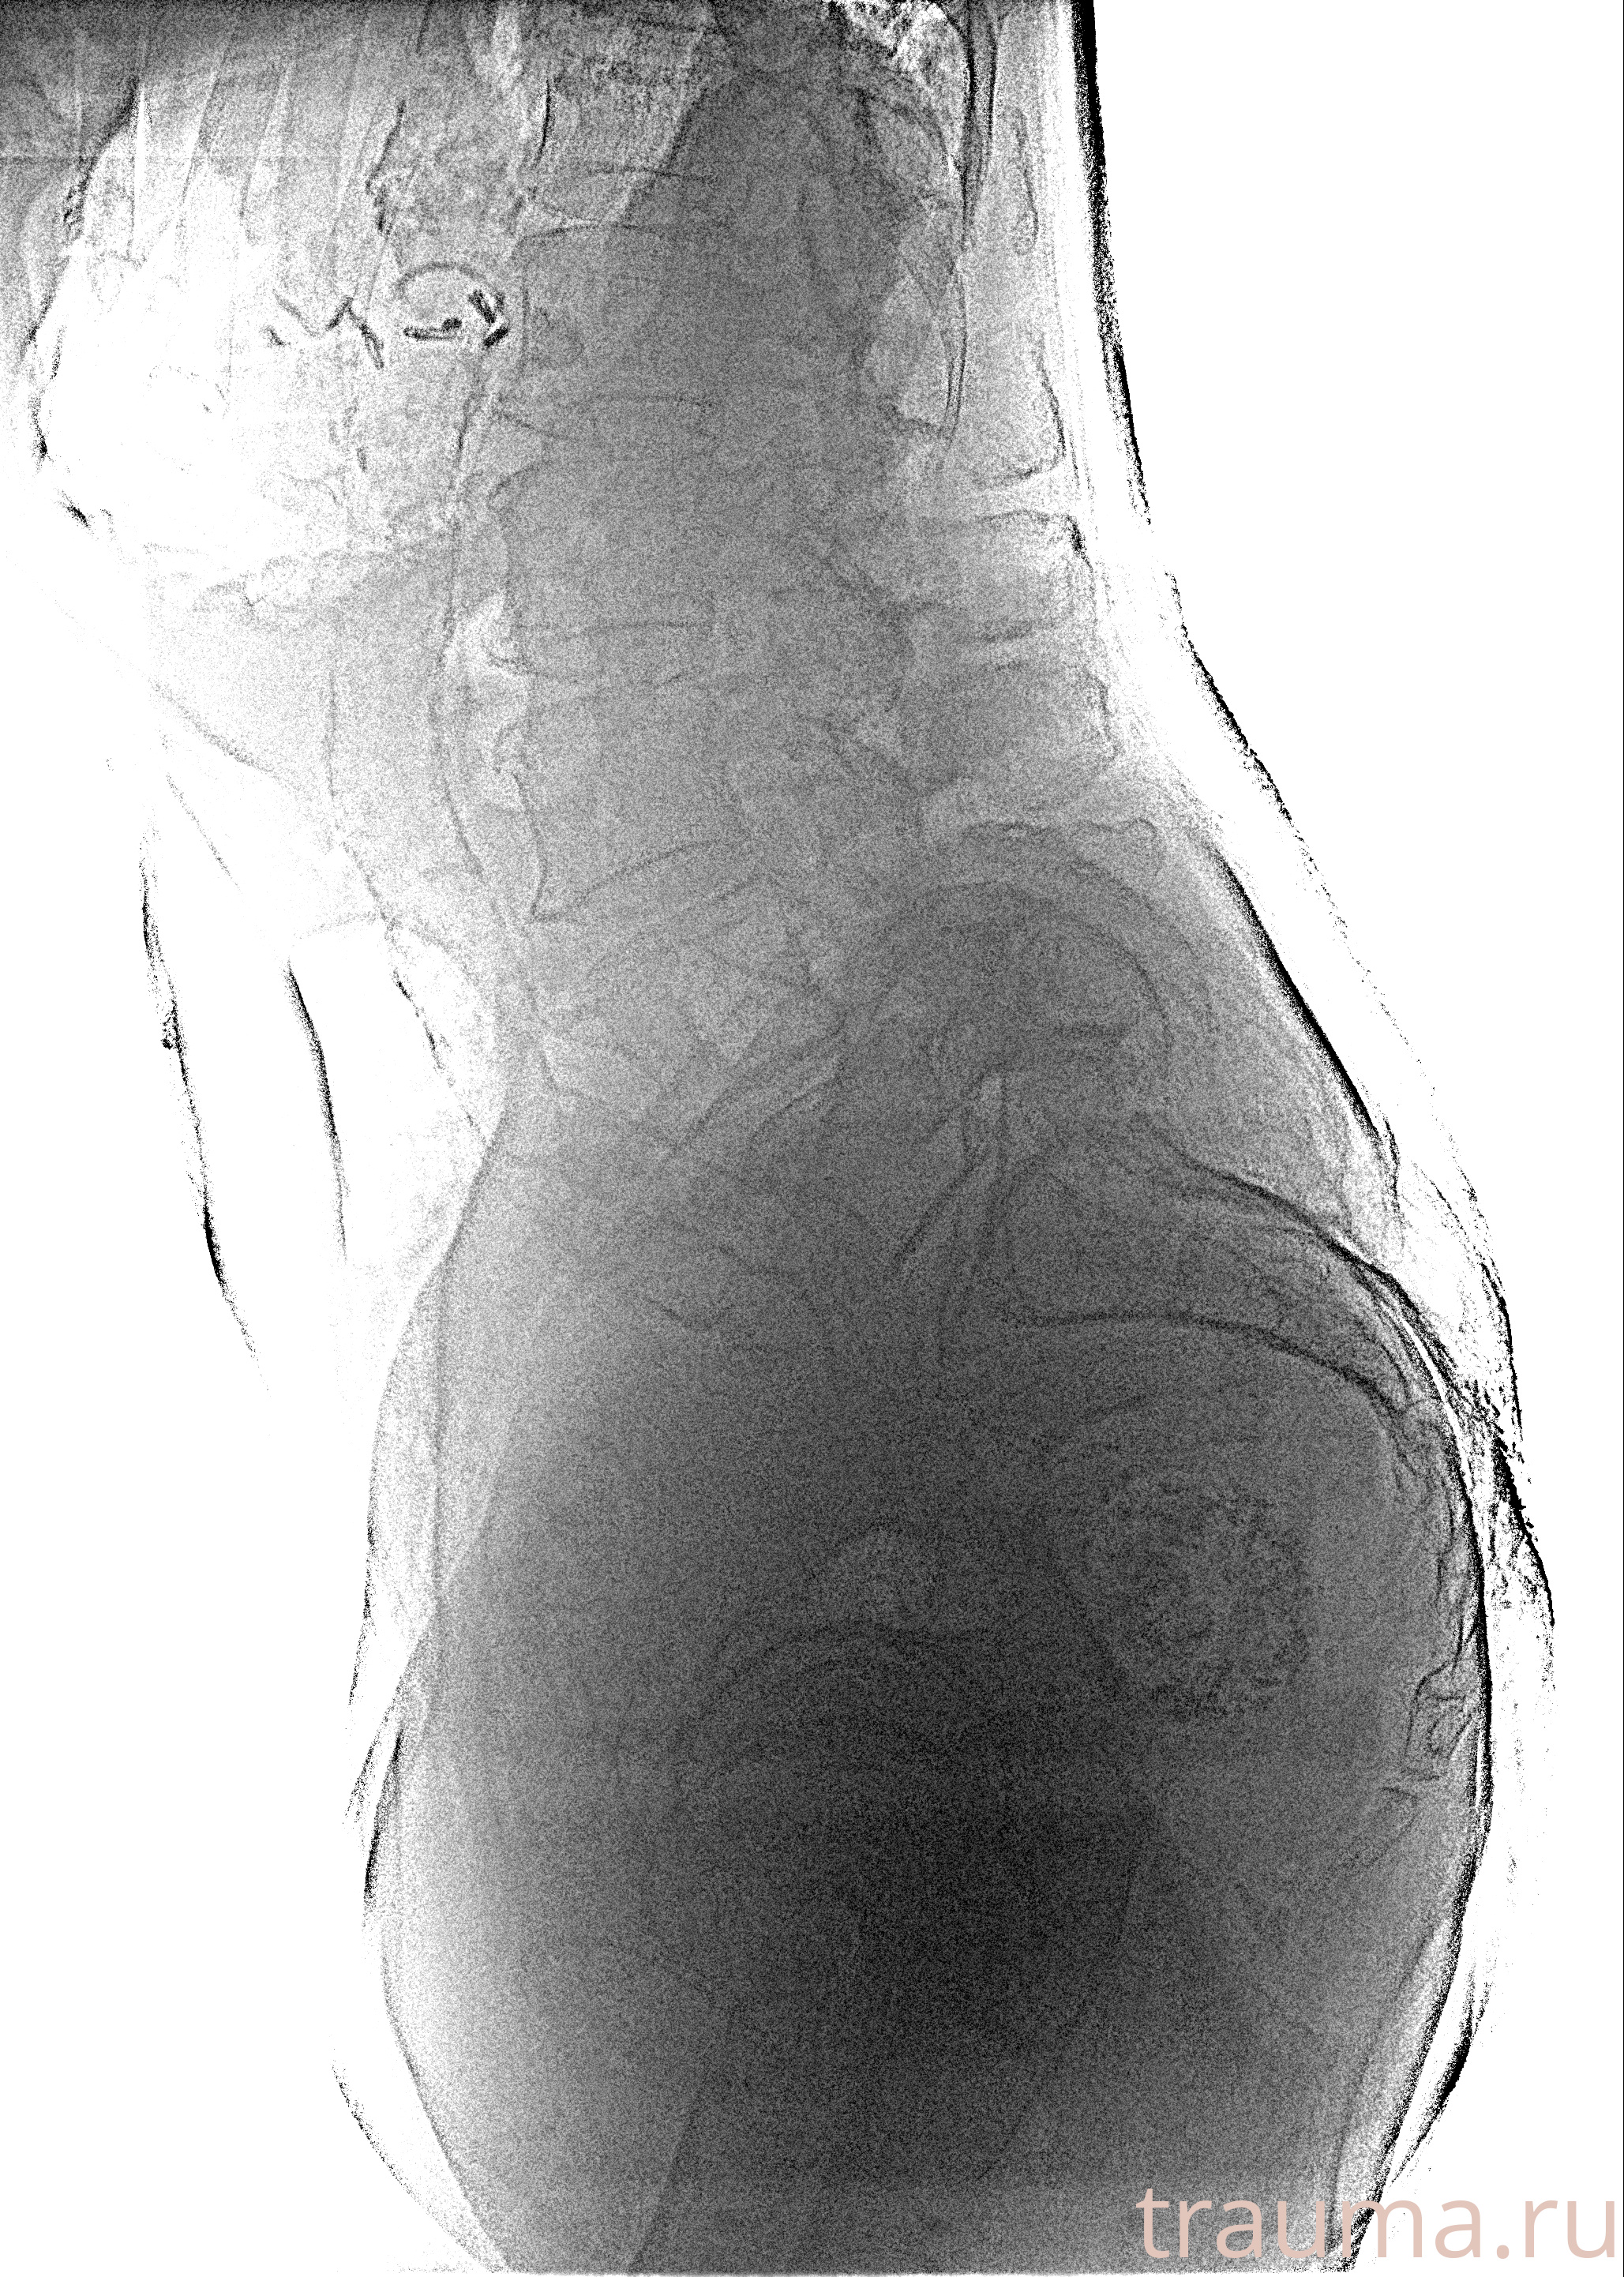

Рентгенограммы

Рентген на дому: по вашему адресу приезжает врач-рентгенолог, травматолог-ортопед с мобильным рентгеновским аппаратом, проводит диагностику травмы или заболевания, делает необходимые рентгенограммы, дает рекомендации по дальнейшему лечению. Получить качественные снимки в домашних условиях возможно благодаря уникальной методике, разработанной МосРентген Центром для института  Склифосовского